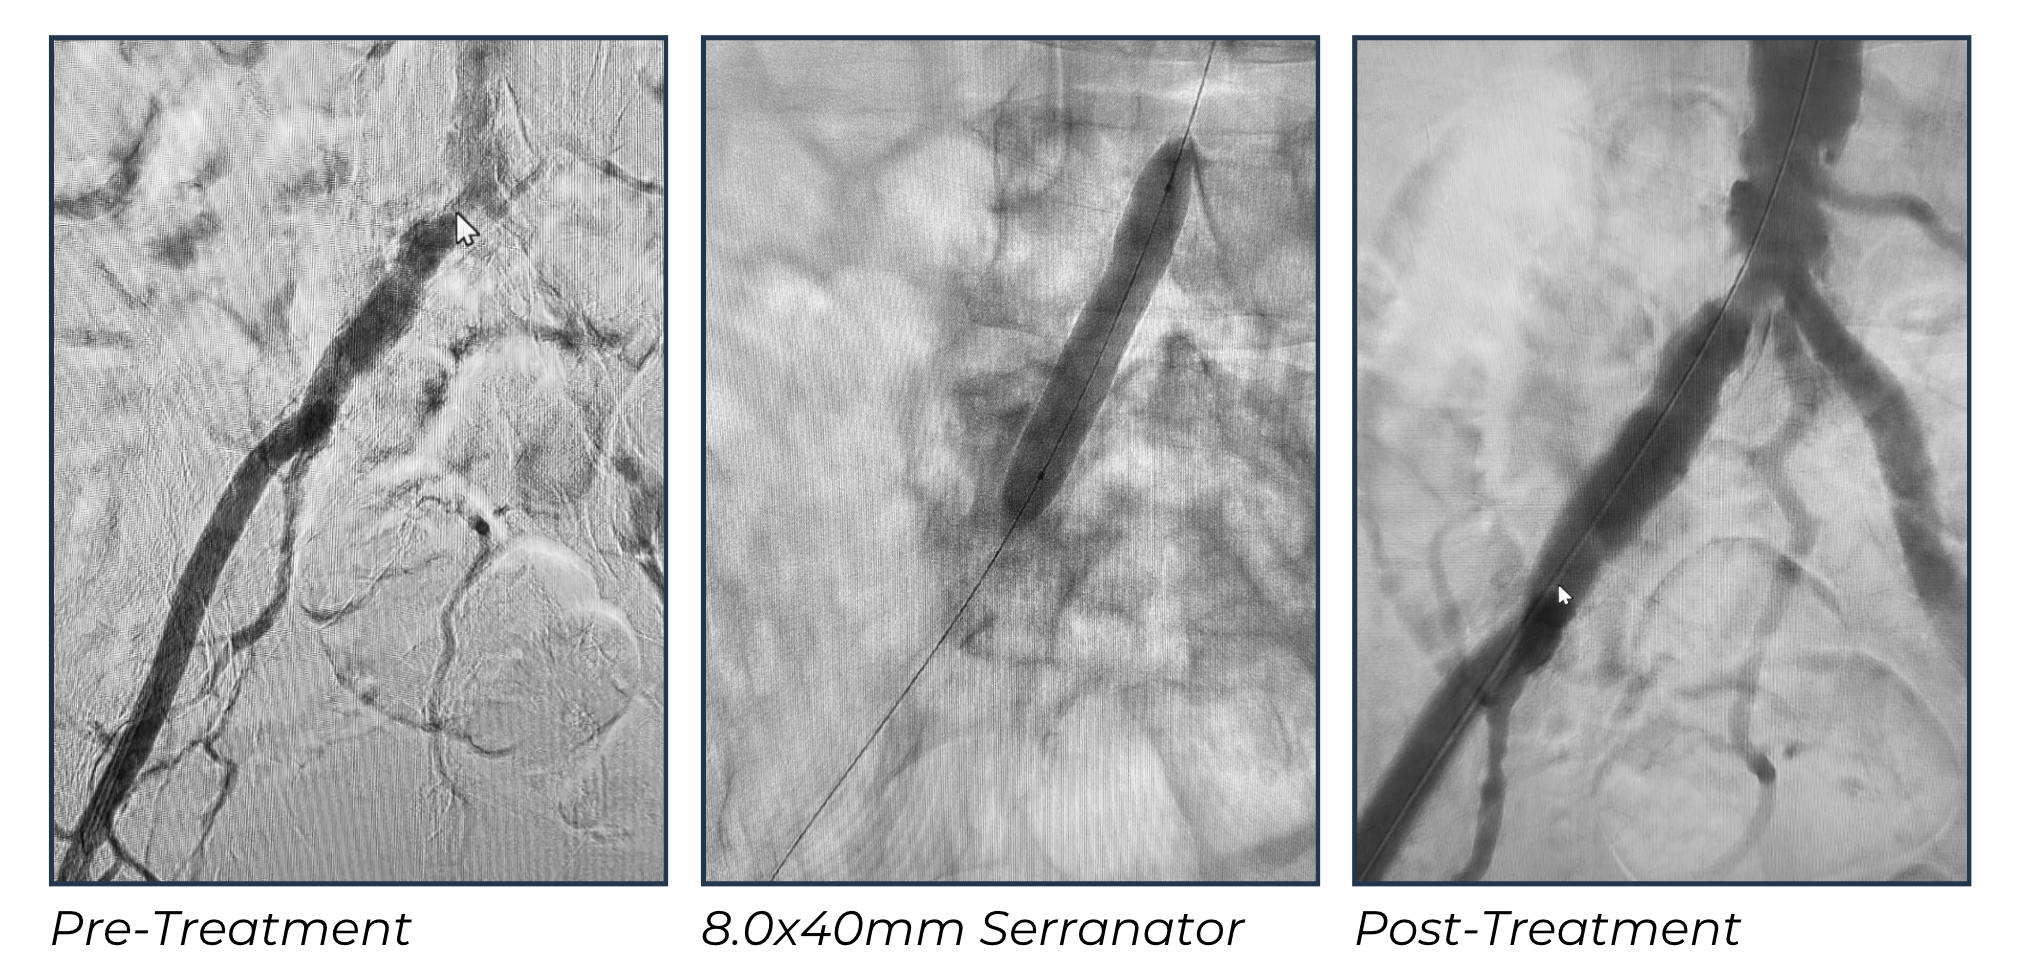

Using an 8.0x40mm Serranator, I was able to treat the lesion with precision and control. The serration technology provided effective luminal expansion while minimizing the risks of dissection and rupture that are commonly associated with POBA.

The procedure was straightforward, with a visible waist on the balloon during inflation that resolved completely at 4 atmospheres of pressure. The technology allowed me to achieve an excellent angiographic result without the need for stent placement. For me, this was a low-risk, high-reward approach that preserved vessel integrity and kept future treatment options open.

The angiographic results were excellent. The initial image showed a severe stenosis at the right common iliac bifurcation, which resolved completely following Serranator inflation. The final angiogram demonstrated near-complete resolution of the lesion and improved flow to the right leg. No dissection, rupture, or other complications occurred. The procedure was efficient, safe, and provided durable results without the use of a stent.